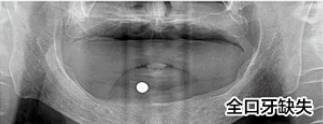

刘先生(花甲之年)牙缺失

步入花甲之年的刘先生其实在40多岁的时候牙齿就开始松动,起初想着还可以凑合吃饭,就没有怎么管,可是如今年纪大了,牙齿一颗接着一颗的掉,只能喝粥。

△检查CT片

经过2个多小时的种植过程,刘先生缺牙问题解决了,当天种好恢复咀嚼力。现场露出一口整齐洁白的牙齿,笑着说:“有个孝顺的女儿真是很大的福气,现在终于可以好好的吃一顿饭了。”